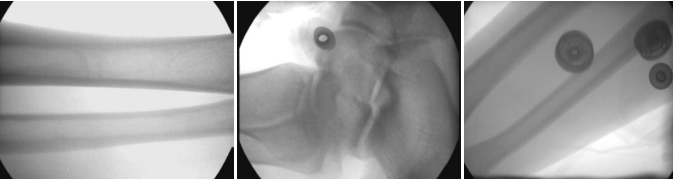

7:拍摄效果图